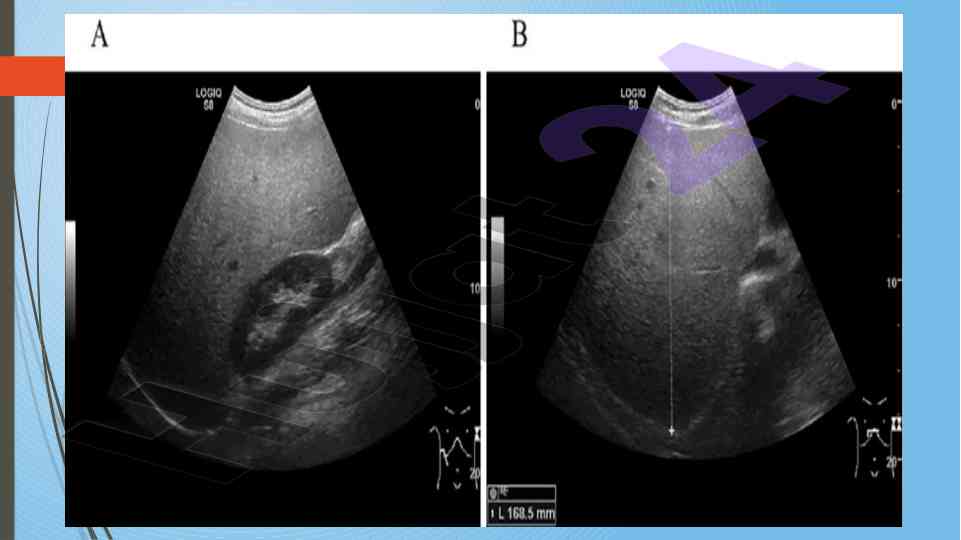

Диссертатсия давомида сурункали гепатитларнинг ультратовуш ташхиси ва этилогиясини ўрганиш. Аутоиммун ва ноалкоголь гепатитларнинг хусусиятлари таҳлил қилинган.